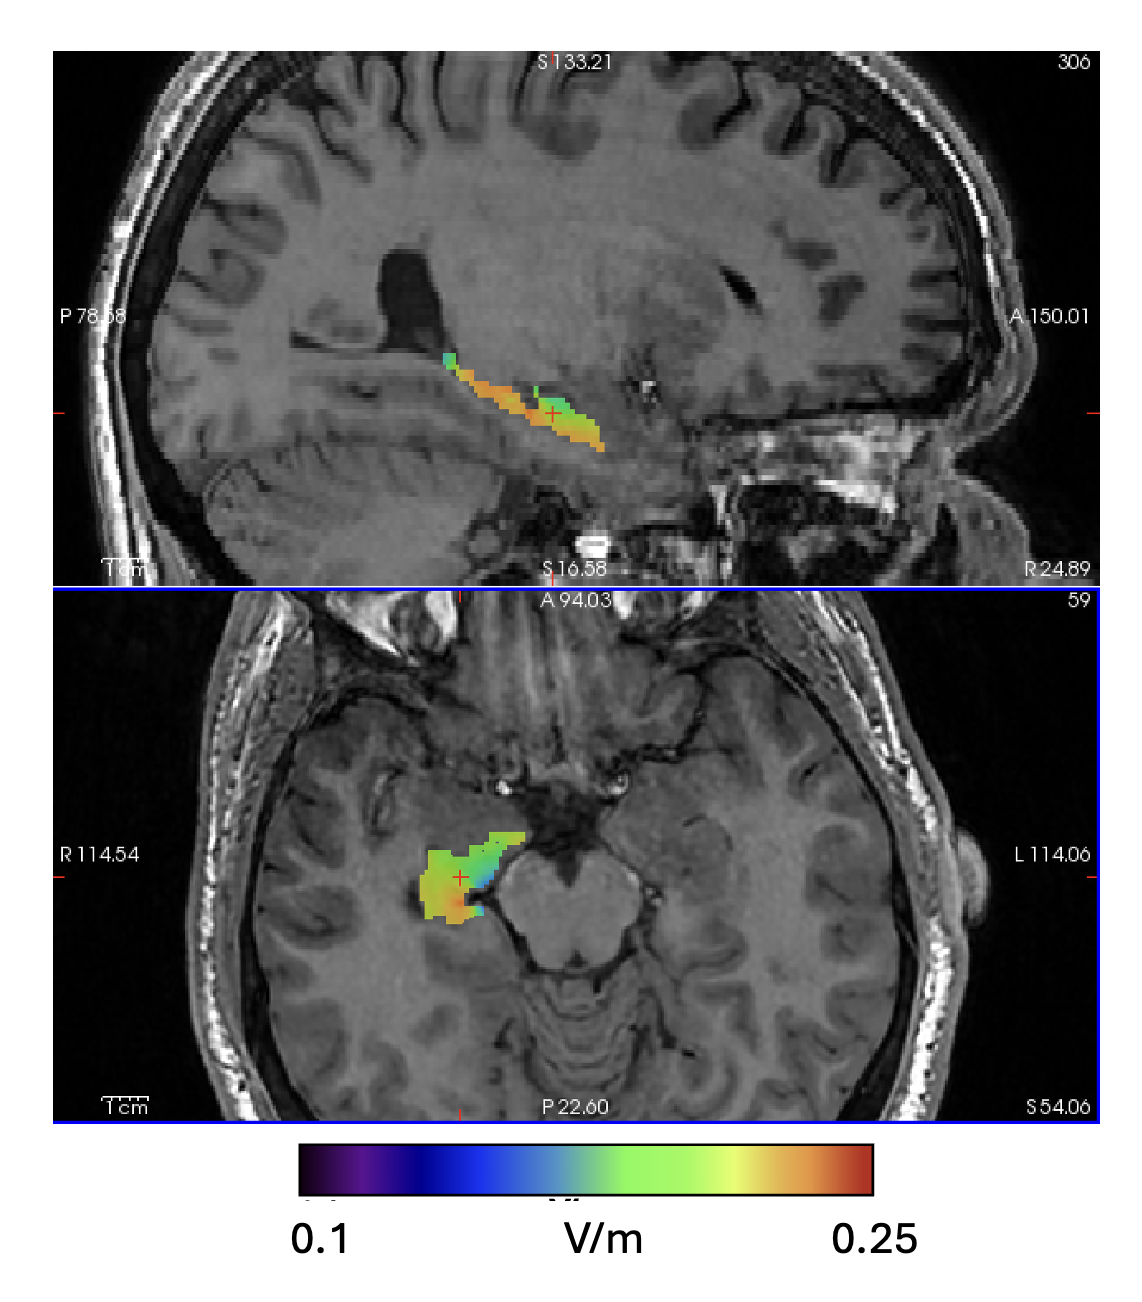

Right Hippocampus ROI analysis showing TI_max field distribution given a 1mA:1mA stimualtion